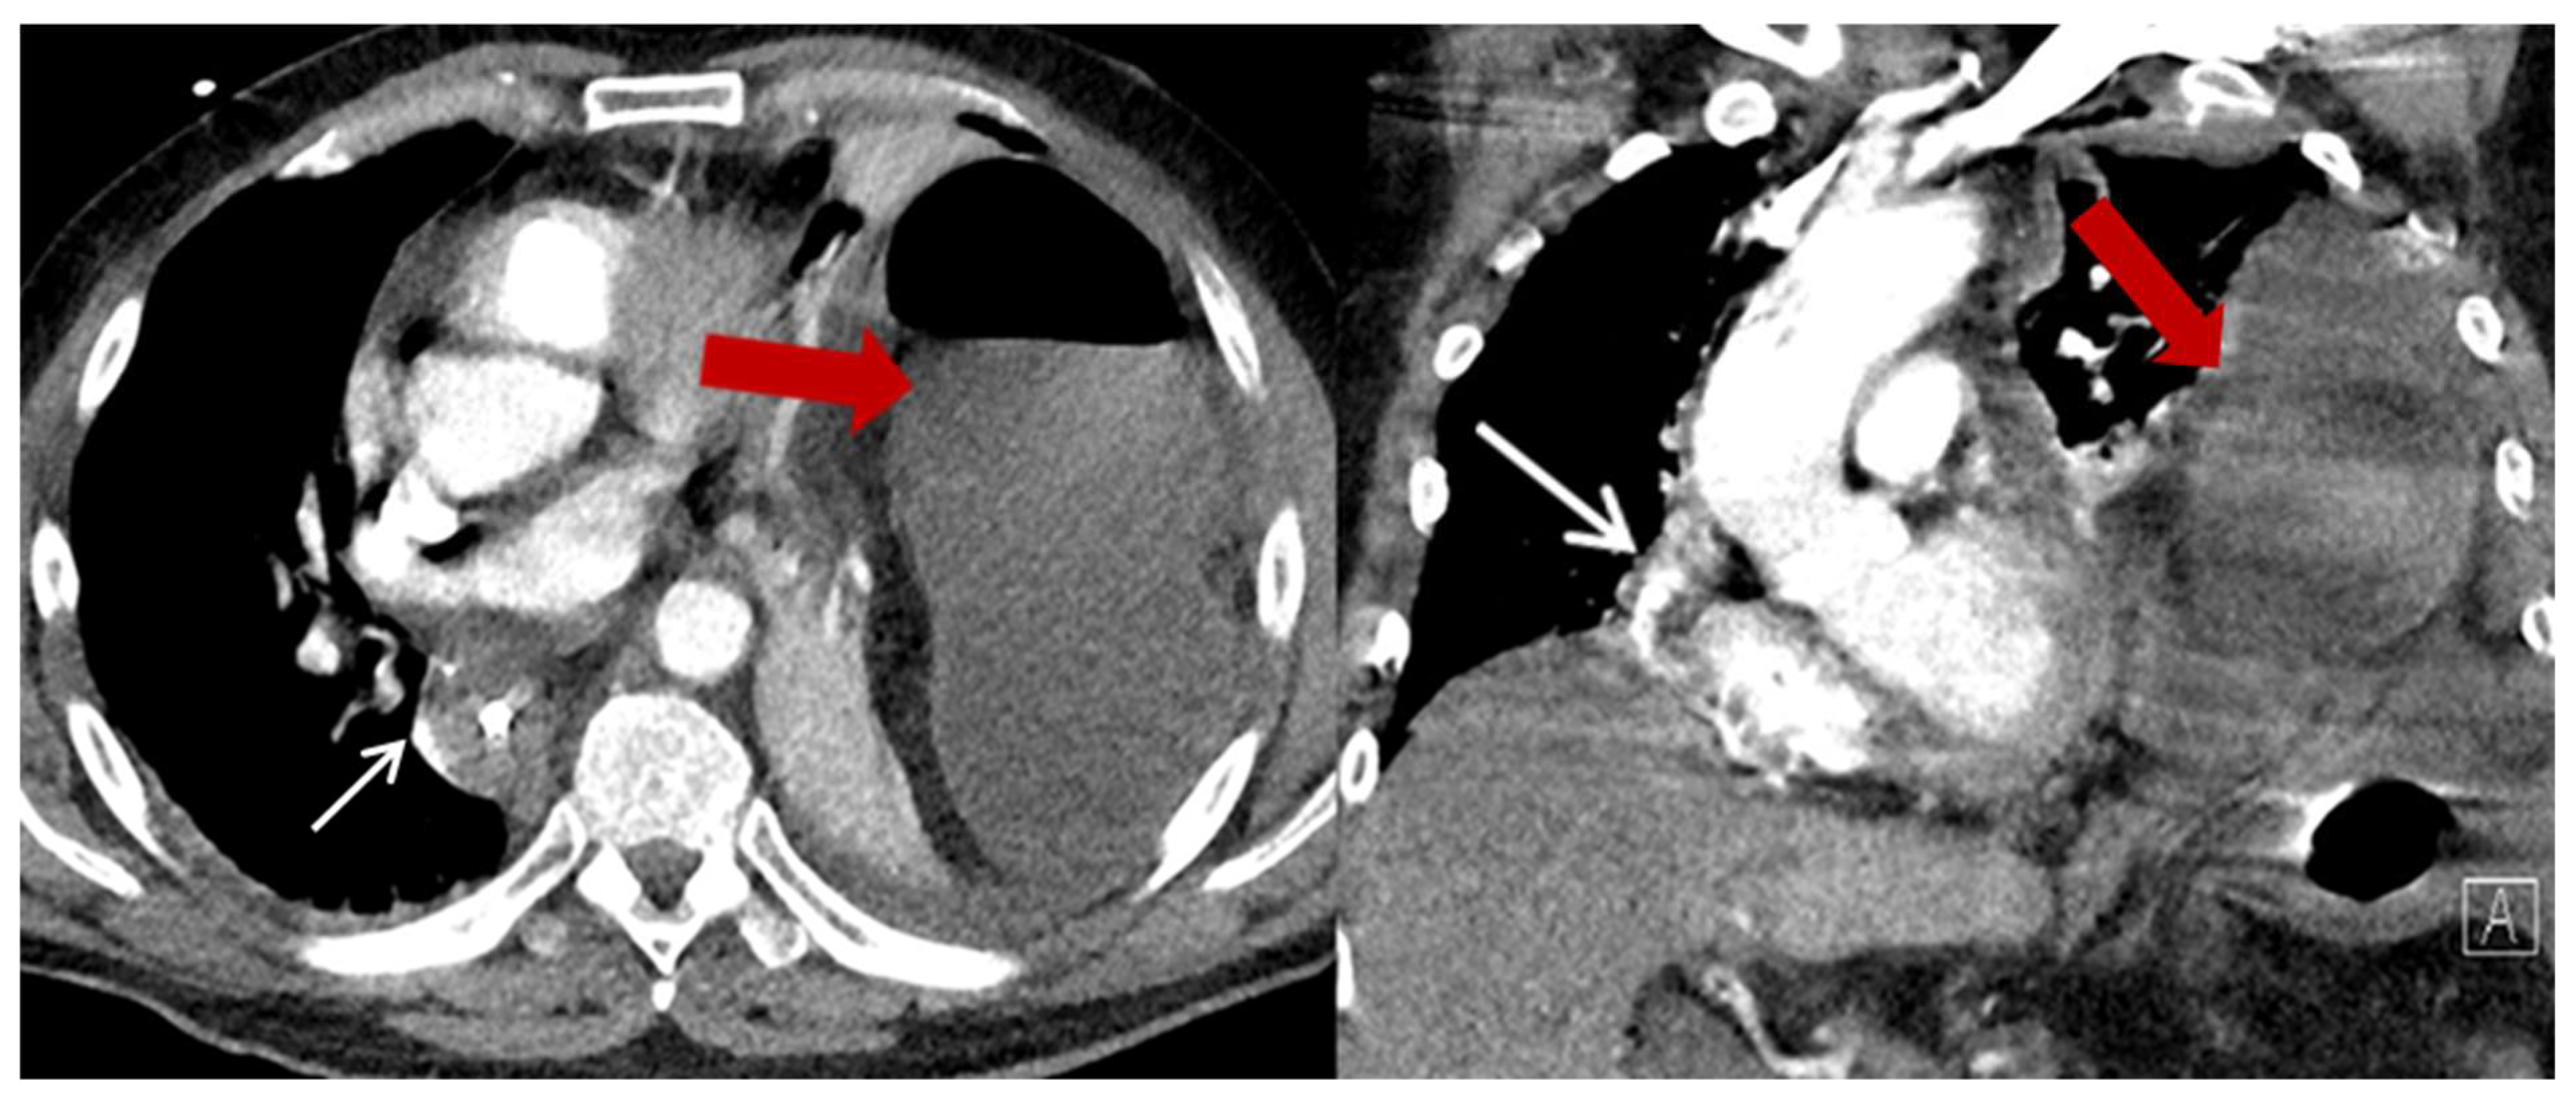

| Characteristics | HH (n = 23) (%) |

| Content of HH, n (%) | |

| Colon | 23 (100) |

| Additionally small bowel | 3 (13) |

| Position of the HH n (%) | |

| Left thoracic side | 18 (78.3) |

| Right thoracic side | 1 (4.4) |

| Both sides | 1 (4.4) |

| Lower mediastinum | 3 (13) |

| Symptoms n (%) | |

| None | 13 (56.5) |

| Abdominal pain and discomfort | 10 (43.5) |

| Ileus/incarceration | 4 (17.4) |